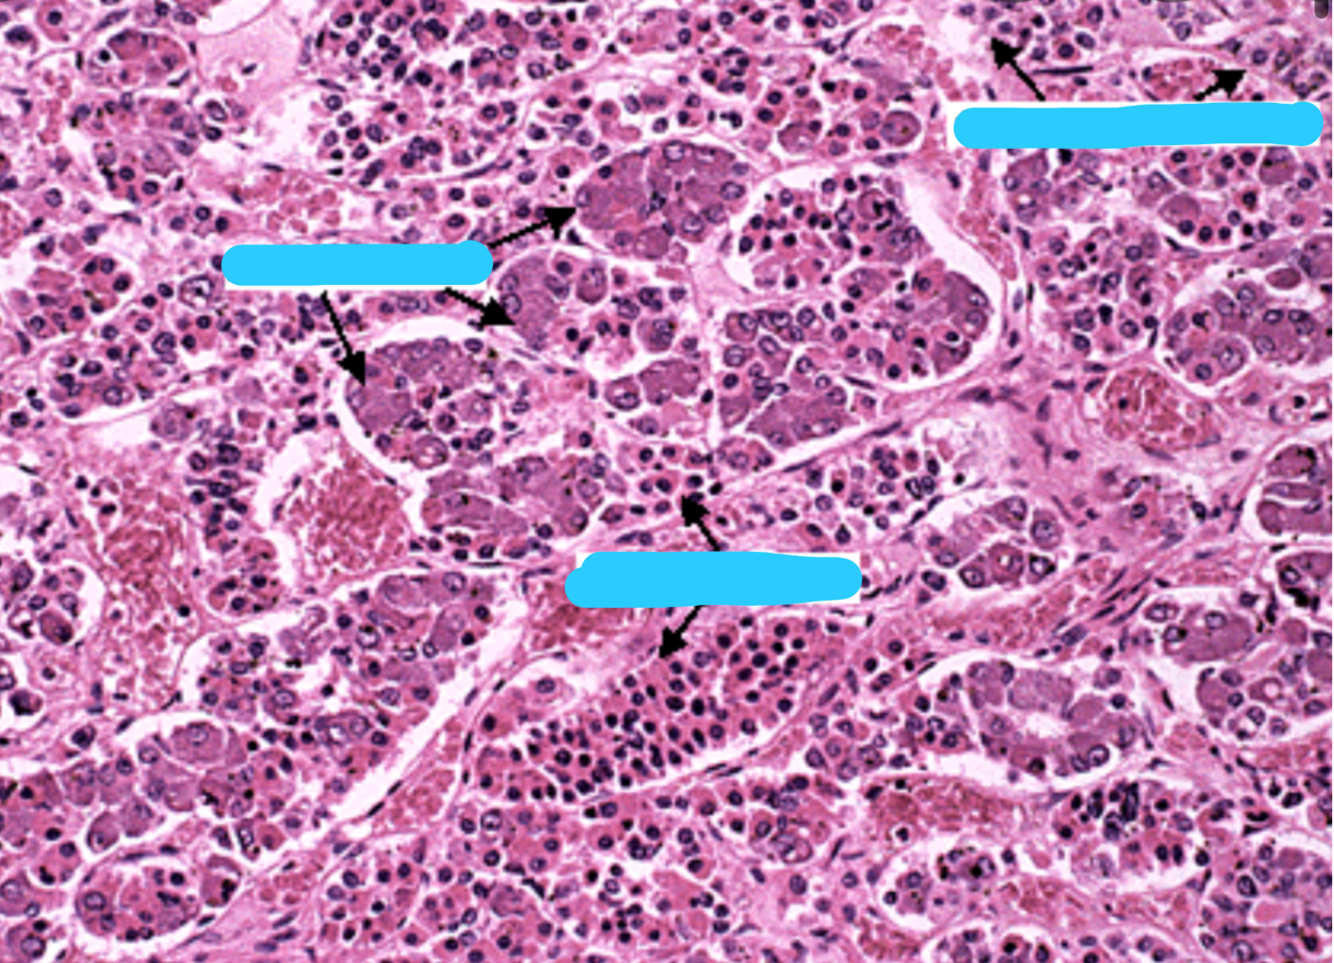

Which part of the kidney is this?

Kidney: Cortex

Renal corpuscles (Bowman’s capsule: simple squamous epithelium)

Proximal convoluted tubules (cuboidal+ microvilli)

Distal convoluted tubules (cuboidal)

Collecting tubule (cuboidal)